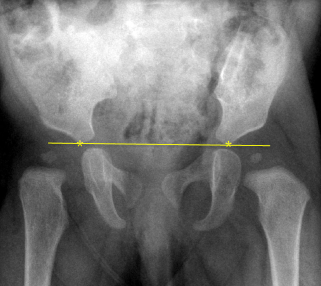

Q what is the name of this measurement? and what is the average + range?

A: Intercrestal Line

assesses the alignment of the L4 body relative to the iliac crests. No average or range is specified.